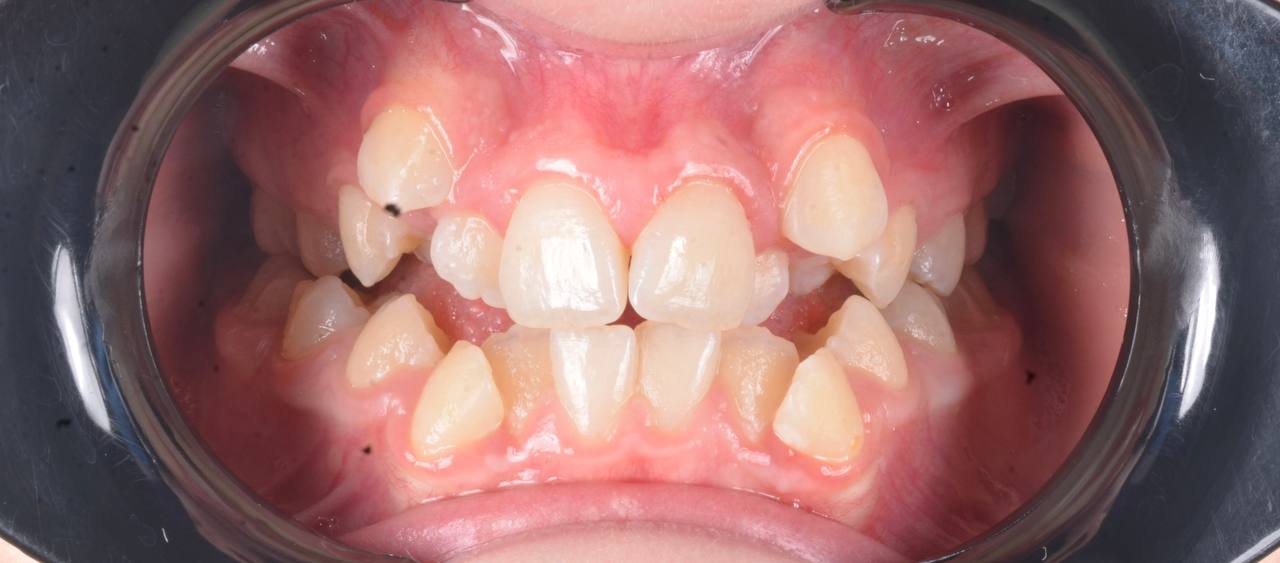

Непростая ситуация, связанная с расположением зубов: лечение кариеса до начала ортодонтического лечения проведено максимально эффективно. Профессионалы своего дела!

Мама мальчика 8 лет обратилась с жалобой: Я вижу, что зуб у сына находится в неправильно положении, возможно ли сейчас это исправить?? Да! Мы достигли результата за 5 месяцев!

У меня всегда было неправильное положение передних зубов. Хочу это исправить!

Мне говорят, что у меня неправильный прикус. Я вижу только кривизну зубов